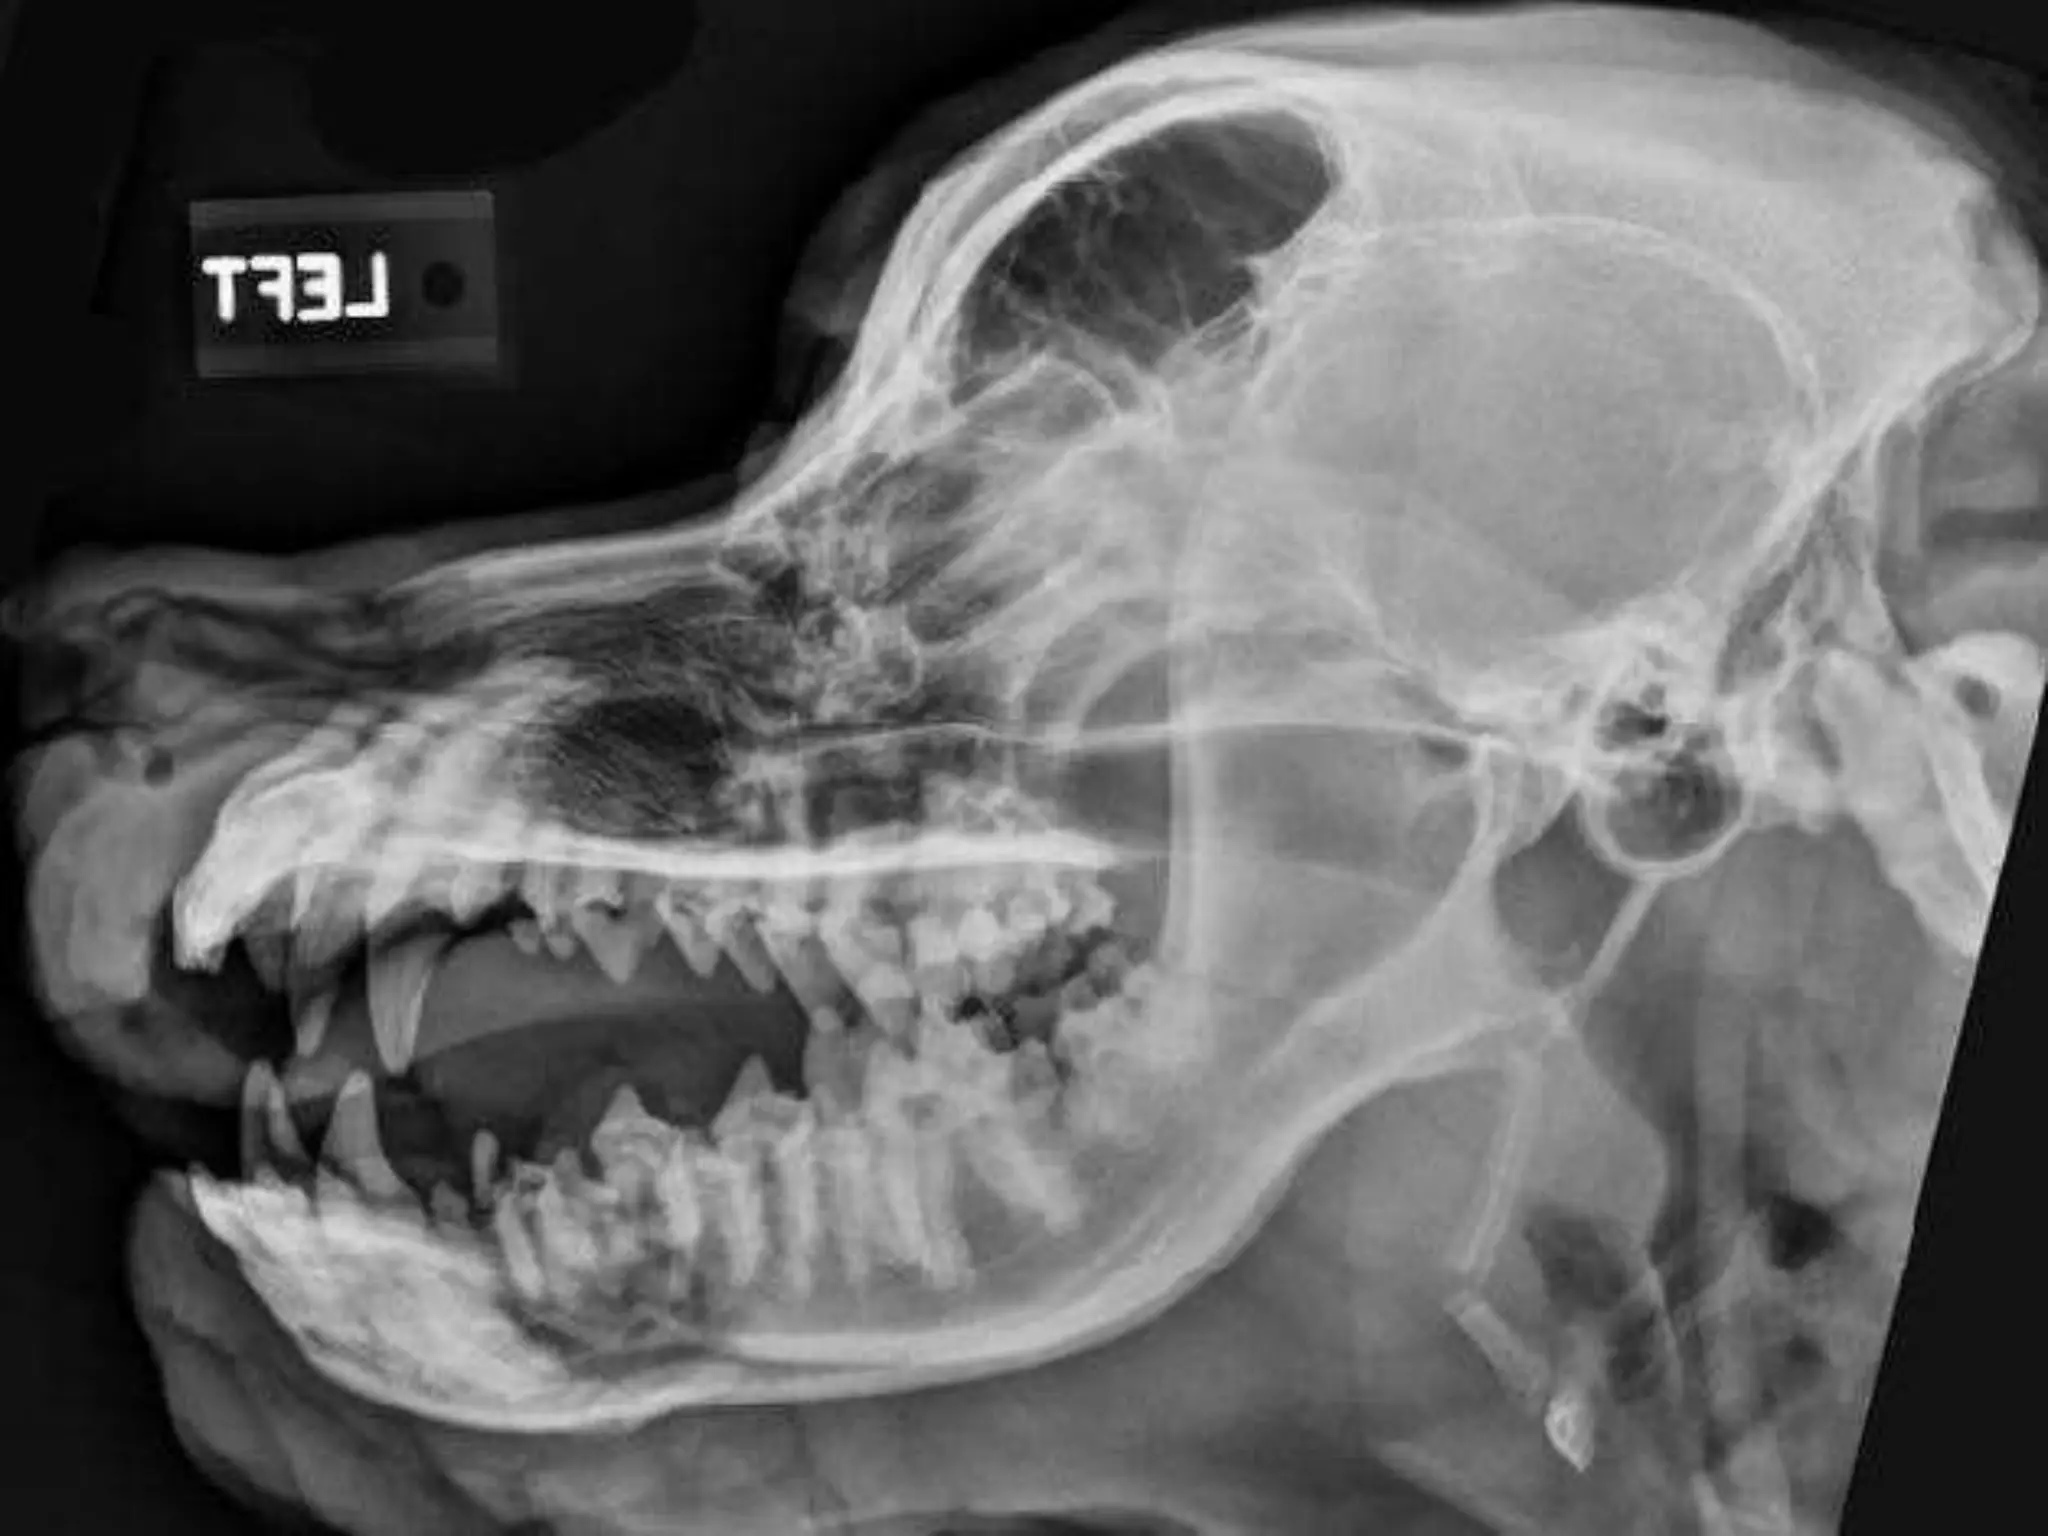

Skull radiology:

Tongue

Hyoid bone

Skull :

-The skull consist of 3 bones combined with

each other to form the skull.

-The skull consist of cranium , mandible and

hyoid bone.

Mandible:

-The mandible consist of body and 2

ramus.

-The 2 halves of the mandible is not

completely fused with each other by the

mandibular symphysis.

-The masseteric fossa is very deep for

the insertion of the masseter muscle.